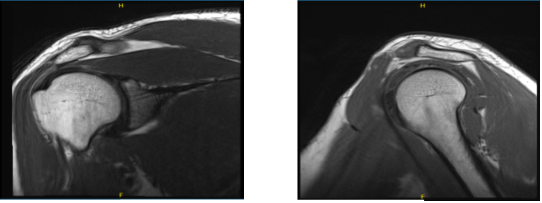

For the past few months, a 36 year-old male patient came to the office due to right shoulder pain. We performed an MRI, which revealed disease in the subacromial and labrum regions. The AC joint is also sensitive for the sufferer. The patient received conservative treatment, but no relief was provided.

MRI findings; Evaluation of the regional osseous structures shows no evidence of marrow edema or contour deformity to suggest bony injury. There is nonspecific subchondral cyst formation at the poster superolateral humeral head. The glenohumeral and acromioclavicular joints are normally aligned.

The acromial process is posterolateral down sloping and its undersurface is generally straight in configuration. The coracoacromial arch closely approaches the underlying supraspinatus muscle/tendon, which may manifest clinically as subacromial impingement.

There is a tear of the inferior insertional fibers of the infraspinatus tendon. The supraspinatus, subscapularis, and teres minor tendons are unremarkable in appearance. There is a partial tear/tendinopathy of the intra-articular biceps’ tendon.

The intertubercular segment of the biceps’ tendon demonstrates normal course and morphology. There is superior labral fraying, as well as stripping of the superior labrum-biceps tendon anchor from the supraglenoid tubercle. This is compatible with a SLAP (superior labrum anterior-posterior) lesion.

The remainder of the glenoid labrum is intact. The regional musculature is well-developed, without evidence of edema or atrophy. There is a small amount of physiologic fluid within the glenohumeral joint.

There is no fluid within the subacromial-subdeltoid or subcoracoid bursae. Incidental note is made of a subcutaneous lipoma within the soft tissues at the posterosuperior aspect of the acromion process. It measures approximately 2.5 cm in greatest dimension.

MRI-3T Right shoulder non-contrast